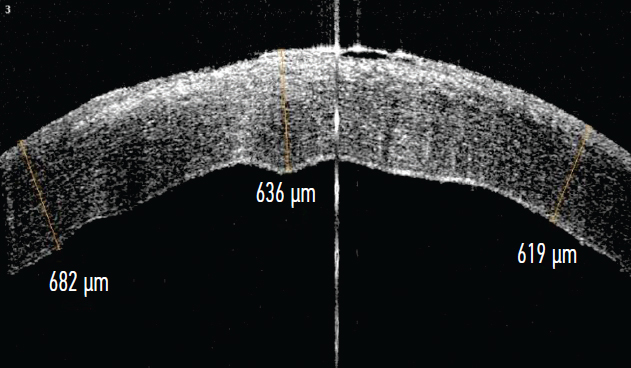

Upon admission, the visual acuity of the left eye was 0.005, it was not corrected. According to OCT data, the cornea is thickened in the area of the epithelial defect to 599–635 microns, the defect size is 2.58 × 2.67 mm (Fig. 3).

Fig. 3. Optical coherence tomography image of the cornea in patient O. upon hospitalization

Рис. 3. Снимок оптической когерентной томографии роговицы пациентки О. при поступлении